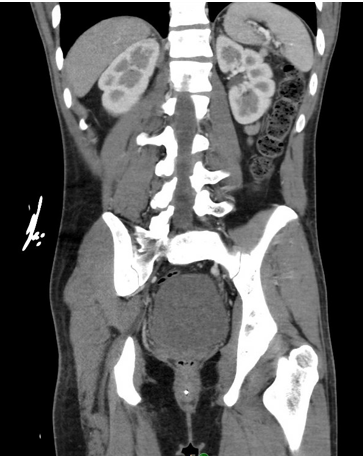

Case Presentation: A 23-year-old man without prior medical history was brought to the ED from his home for profound somnolence which had progressed over two days. EMTs at the scene noted that the patient was sluggishly responsive to painful stimuli. Initial vital signs were within normal limits, and a point-of-care glucose check was 28 mg/dL. He was given IV glucagon, and upon arrival to the ED, he had become slightly more interactive.Physical examination revealed a tired, but well-nourished young man with diffuse tan and hyperpigmentation of his buccal mucosa and palmar creases. Initial blood work showed microcytic anemia and thrombocytopenia (Hgb 7.5, platelets 126). A metabolic panel revealed normal hepatic enzymes, elevated creatinine, hyponatremia, and hyperkalemia (Cr 1.4, Na 121, K 5.7, CO₂ 18). A toxicology screen and respiratory pathogen panel were unremarkable. A CT scan of the abdomen and pelvis revealed bilaterally atrophic adrenal glands, with no other intra-abdominal abnormalities. Based on these findings, the patient was suspected to have adrenal insufficiency and was treated with IV hydrocortisone and fluids.Overnight, the patient became suddenly bradycardic with a heart rate in the 20s and subsequent decline in responsiveness. He received inotropic support, which led to a quick improvement. Further serology indicated severe hypothyroidism, with a TSH level >50.00 and free T4 < 0.25. He was diagnosed with myxedema coma following adrenal crisis, with an underlying etiology of autoimmune polyglandular syndrome type 2 (APS II). A thorough endocrinological evaluation revealed antibodies to 21-hydroxylase, thyroid peroxidase, and intrinsic factor.After several weeks of treatment with mineralocorticoids and thyroid hormone supplementation, the patient returned to normal life activities. Follow-up studies showed that his metabolic abnormalities and cytopenia had largely resolved.